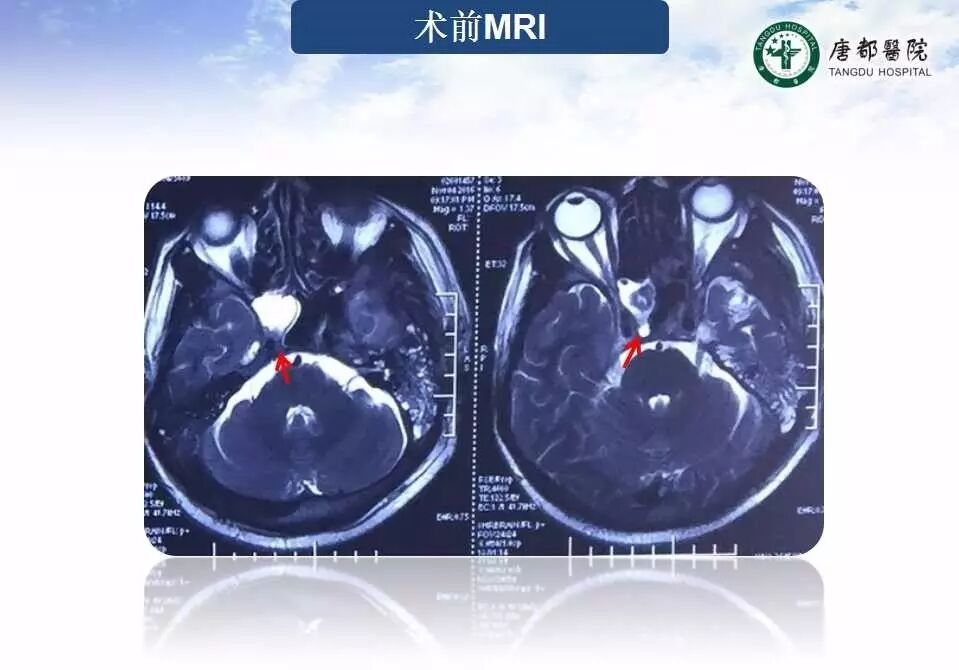

Case 1

长按并识别二维码即可查看该手术视频